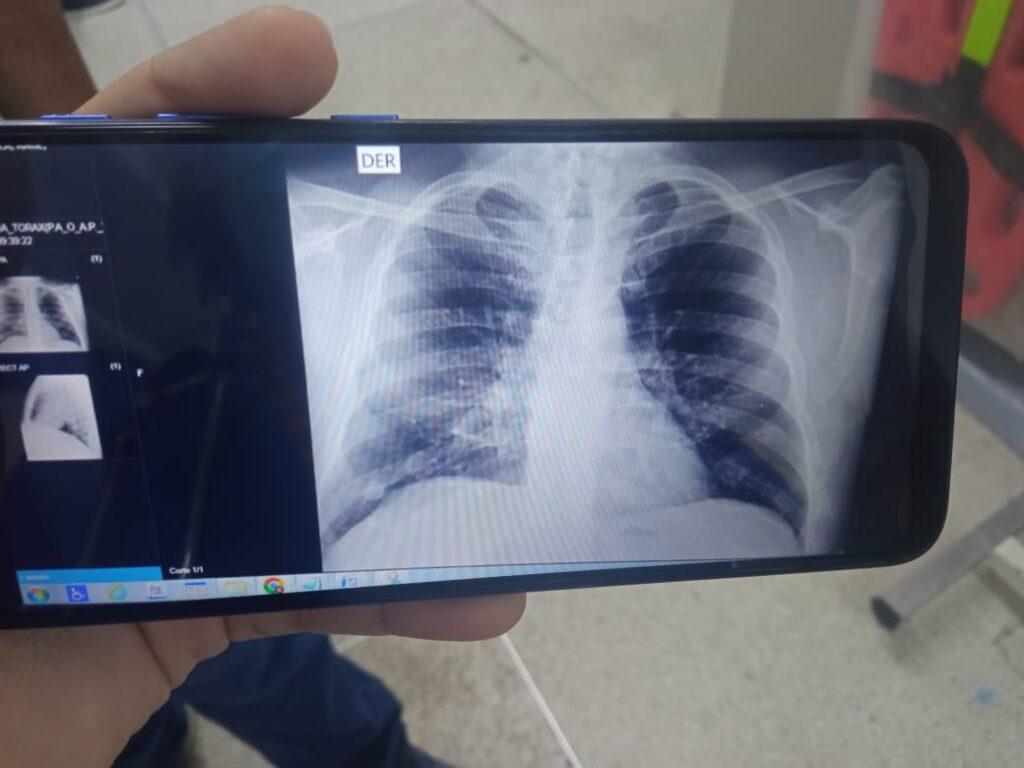

Fotografía de la radiografía de los pulmones de Raul Pardo, con un compromiso del 95%, su pronostico era reservado.

Corría el año 2020 y el mundo se había detenido. Las calles vacías, los rostros cubiertos, los abrazos prohibidos. Raúl, un hombre fuerte, pensionado de la Policía y trabajador de la Universidad de Cartagena, se convirtió en uno más entre los millones contagiados. Pero no fue uno más. Su cuerpo fue tomado por el virus con una fuerza demoledora: el 95% de sus pulmones comprometidos. Lo desahuciaron.